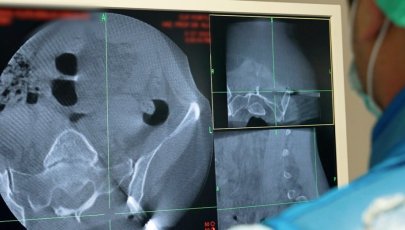

• Exames imagiológicos como ressonâncias magnéticas e TACs